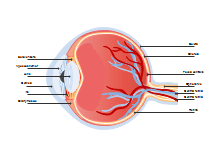

illustrazione scientifica - anatomia umana